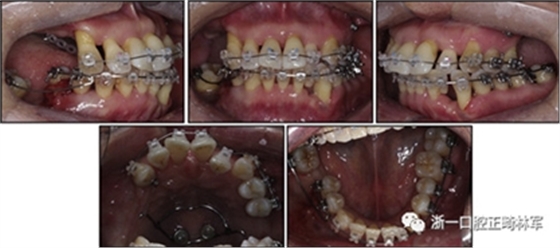

一名因多顆牙齒缺失和牙周損傷的49歲婦女被牙周科送往國民健康保險服務一山醫(yī)院的正畸科進行跨學科綜合治療。多顆后牙已在10天前被拔除。她的主訴是前牙列擁擠,她想改善美觀和功能。她的病史沒有提供有用信息,她沒有顳下頜關節(jié)紊亂的跡象。口外檢查顯示面部對稱,休息位時嘴唇不適,尖銳鼻唇溝和突出的嘴唇。她的下頜牙齒中線偏移到面部中線的左側(圖1)。

圖1. 治療前面部和口內照片

口腔內由于牙周炎,她的上頜右側第一和第二前磨牙,上頜右側第一和第二磨牙,上頜左側第一和第二磨牙以及下頜右側第一磨牙缺失。牙周探查顯示在磨牙區(qū)域和下頜骨左側側切牙區(qū)有深的牙周袋,還存在出血(表I)。上頜骨和下頜骨前牙擁擠,左側側切牙存在反合,下頜左側側切牙發(fā)過度萌出。覆蓋是5毫米,上頜切牙是唇傾的。在上頜弓中,尖牙和前磨牙是近中傾斜,右側尖牙過度萌出。而且,下頜右側第二磨牙向近中傾斜。尖牙處于I類關系,但無法評估磨牙關系(圖1和2)。

圖2. 治療前牙齒石膏模型